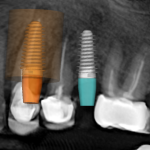

- Giai đoạn 1: nhổ răng nhiễm trùng R23,24 + đặt 2 trụ implant có ghép xương và làm răng tạm tức thì

Giai đoạn 1: nhổ răng nhiễm trùng + đặt 2 trụ implant có ghép xương